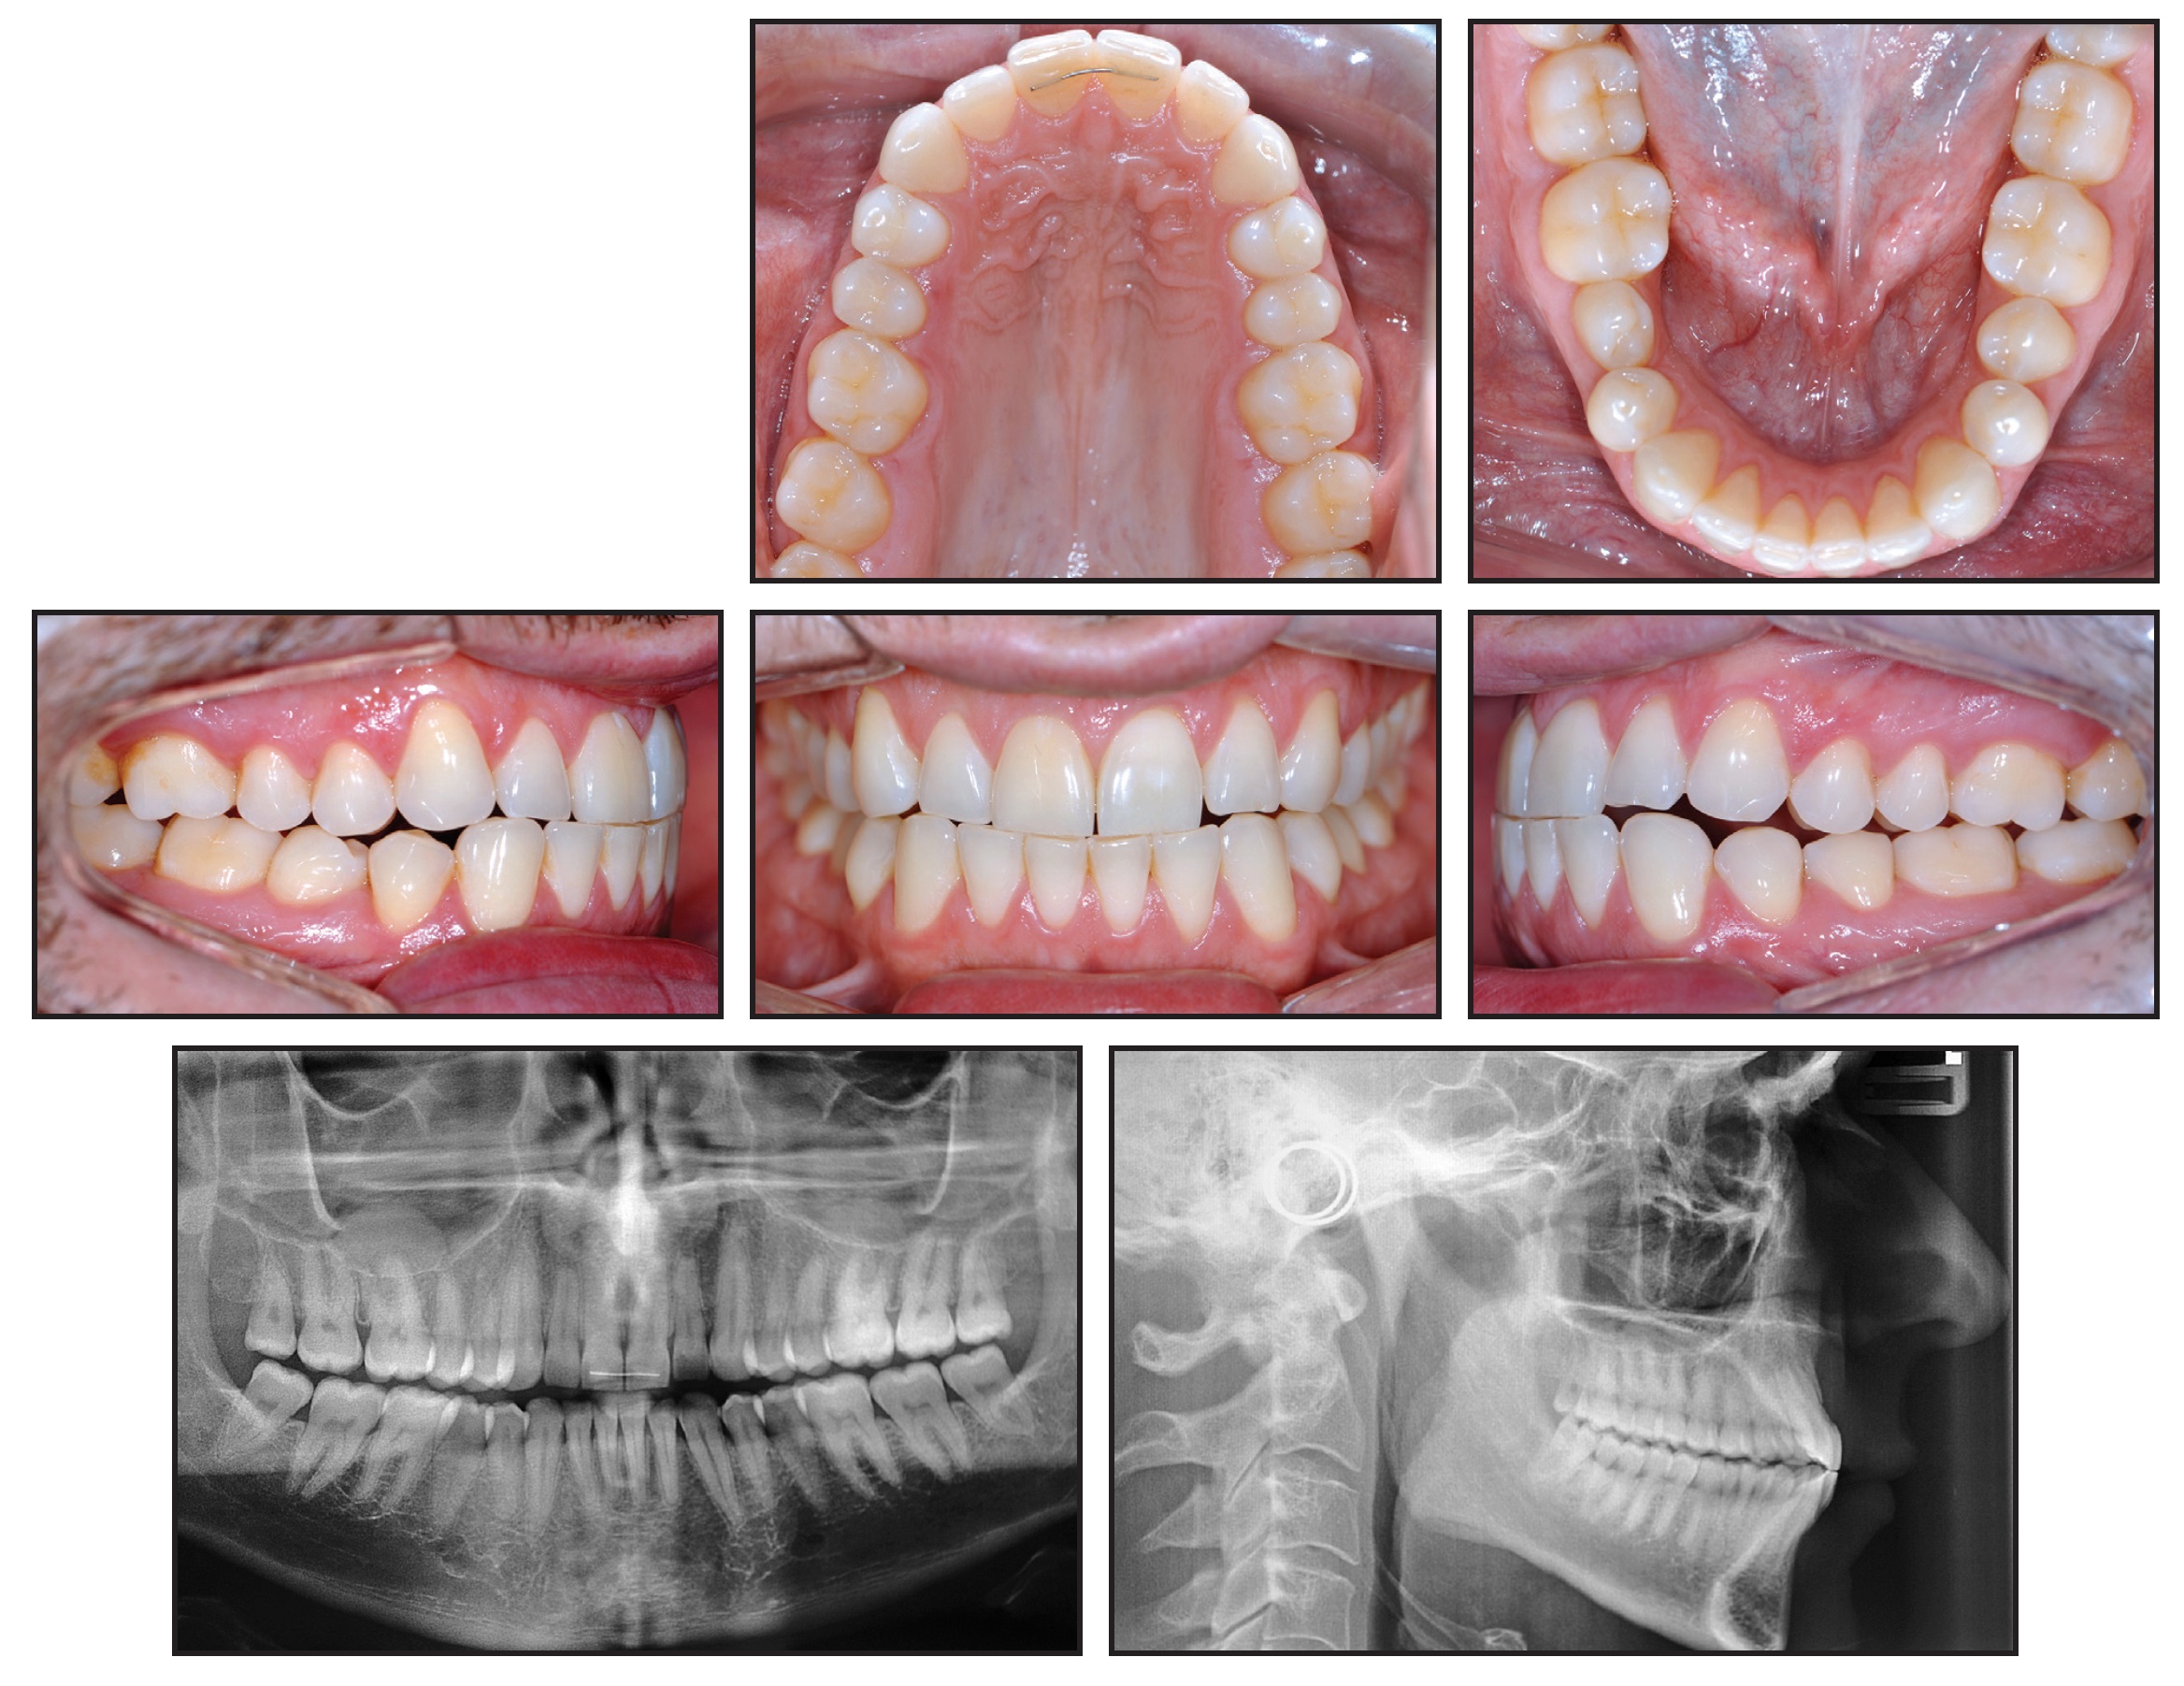

February 2026 Issue HighlightsOVERVIEWBiomechanical Principles and Techniques for Management of Maxillary and Mandibular Second MolarsThe authors review orthodontic biomechanics used to control maxillary and mandibular second molars during comprehensive treatment. Emphasis is placed on anchorage considerations, torque control, bite-opening strategies, and clinical techniques for managing erupted, partially erupted, or impacted second molars.